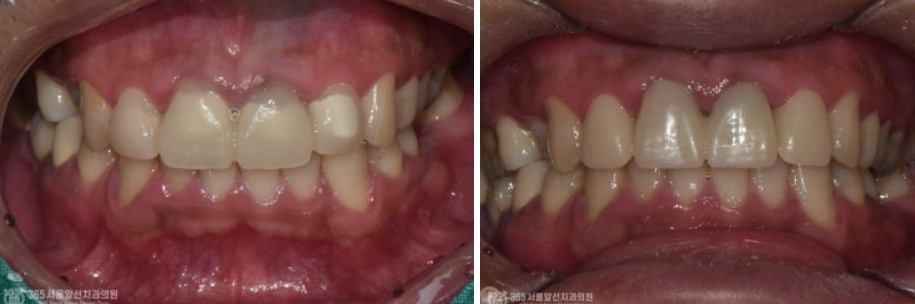

위쪽 앞니 보철물을 한지 오래됐는데, 바꾸고 싶어요. 안녕하세요. 주안역치과 365서울앞선치과 대표원장 강동우입니다. 오늘 소개해드릴 치료 증례는 앞니 보철물이 어색하다는 불편감으로 내원하신 환자분의 증례입니다~ 앞니는 치아의 기능도 중요하지만 무엇보다 심미성이 중요합니다. 쉽게 말해 앞니는 이쁜게 중요하다고 볼 수 있습니다 ㅎㅎ 촬영일시 : 2024.05.03. 처음 내원 당시 정면 모습입니다. 환자분께서 나이가 젊으셨음에도 불구하고 앞니의 보철물의 색상이 탁하고 어두워보이며 심지어 앞니 끝부분이 깨져있는것도 보입니다. 또한 PFM이라고 내부에 금속구조물을 포함한 보철물이다보니 금속 구조물이 빛의 투과를 막아 잇몸색이 탁한 색으로 보이는 우산효과(umbrella effect)도 관찰됩니다. 촬영일시 : 2024.05.03. 내원 당시 치료전 엑스레이입니다. PFM으로 제작된 앞니 보철물이 관찰되며, 치아 내부에 신경치료가 행해졌던 흔적도 보입니다. 환자분께서 증상은 따로 없으셨으나, 신경치료 상태가 불량하여 재신경치료도 진행하기로 했습니다. 촬영일시 : 2024.05.03. 재신경치료 중에 촬영한 엑스레이입니다. 정확하게 신경치료가 이루어지고있는것이 관찰됩니다. 촬영일시 : 2024.05.03. 재신경치료 후 엑스레이 사진입니다. 깔끔하게 충전된 양상이 관찰됩니다. 촬영일시 : 2024.05.03. / 2025.08.02. 이제 심미의 완성을 위한 잠정보철물(Provisional restoration)을 제작하여 환자분께서 원하는 형태를 찾아가며, 잇몸의 형태도 조절하는 과정(gingival molding)을 진행합니다. 환자분께서 심미를 중요시 여기는 분이셔서 두 번에 걸친 임시치아 제작 단계를 거쳐 최종적인 보철물을 만들었습니다. 촬영일시 : 2025.08.02. 완성된 최종보철물입니다. 깔끔하게 잘나왔습니다 어두웠던 잇몸색상도 개선되었습니다. 환자분께서도 만족하셨습니다 ㅎㅎ 촬영일시 : 2024.05.03. / 2025.08.02. 치료 전후 비교 모습입니다. 드라마틱한 변화가 관찰됩니다. 오늘은 오래된 앞니 보철물 교체에 관한 주제로 증례를 소개해드렸습니다. 앞으로도 좋은 치료로 보답하는 석바위시장치과, 365서울앞선치과가 되겠습니다 ! [ 치료기간: 2024년 5월3일 ~2025년 8월 2일 ] ※ 365서울앞선치과의원의 모든 포스팅은 각 진료과 의료진이 직접 작성합니다. 365서울앞선치과의원 블로그의 임상 케이스 게시물은 환자분께 의학적으로 정확하고 상세한 정보를 드리기 위해 각 진료과 의료진이 직접 작성하며, 모든 증례 사진은 본원 의료진이 직접 시술한 증례를 촬영한 것으로, 의료법 제23조, 제56조에 의거하며 환자분의 동의를 얻어 포스팅에 사용하였습니다. 또한 해당 케이스는 본 환자분의 치료 결과이며, 환자 상태에 따라 치료의 결과는 달라질 수 있습니다. |